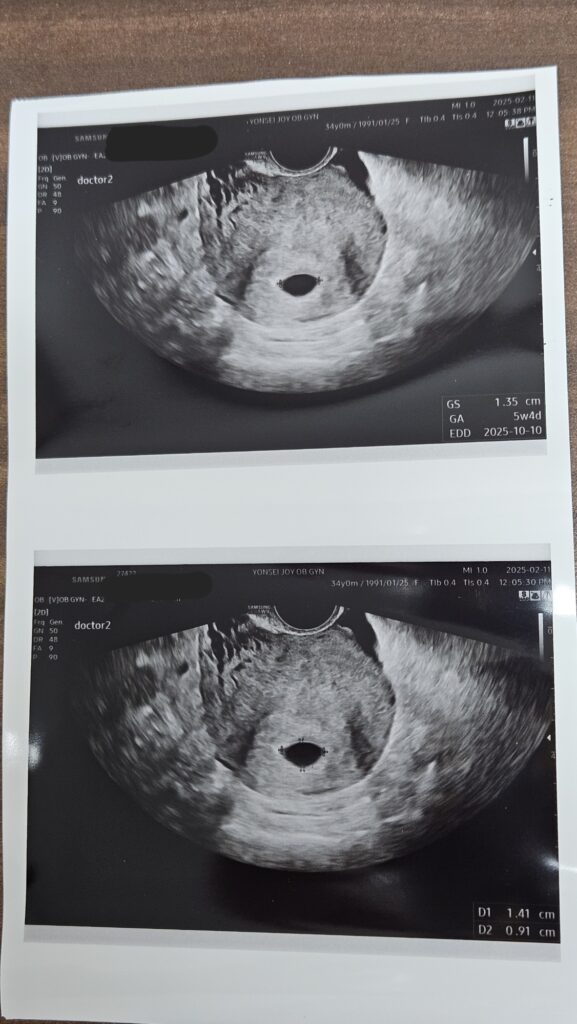

피검사 후, hCG 수치를 토대로 아기집이 보일만한 날짜를 받아서 그 날짜에 맞추어 다시 병원에 방문해서, 드디어 첫 초음파를 보았다.

이 때 5주 4일이었다.

초음파상 아기집이 비어 보여서 조금 걱정이 되었던 것 같다.